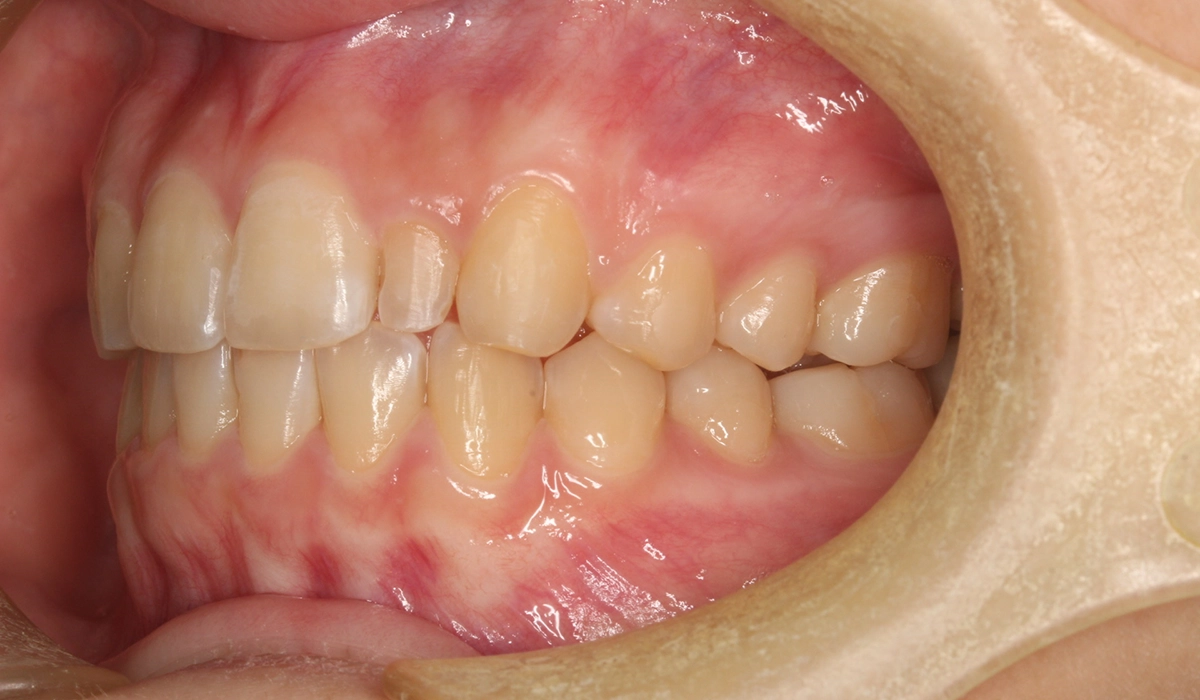

術前:左側

術後:左側